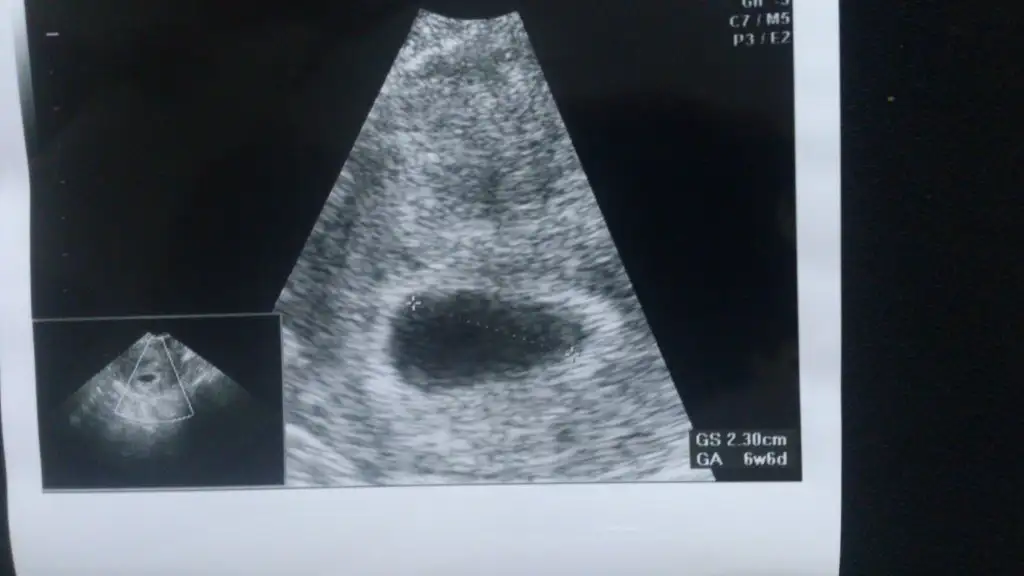

Bak burda bebiş gorunuyor...benim kesede bu şekilde ama içinde bebek gorunmuyor....yolladığım fotoyu gordunmu....en iisi biraz sabır edeyim rabbim yuzumuzu guldursun ya ne olurrrrEyham bak canım burada 5 haftalık kese solda ama bebek kese içinde sağda